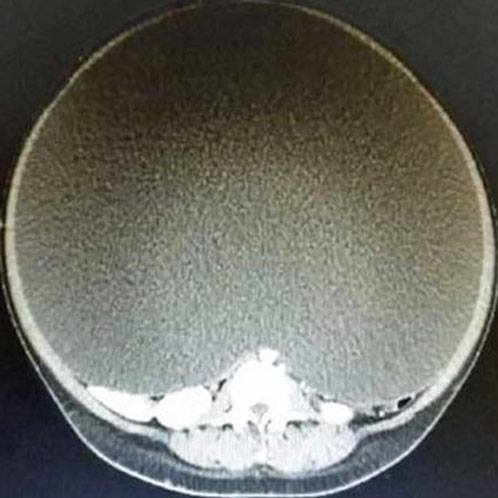

24 yaşındaki bir kadın, diyet yapmasına rağmen gittikçe kilo aldığını fark etti. Ancak tuhaf olan yüzü, kolları ve bacakları zayıflarken karnı günbegün şişiyordu. Karnındaki şişlik organlarını o kadar rahatsız ediyordu ki birkaç adım attıktan sonra acı içinde nefes nefese kalıyordu.